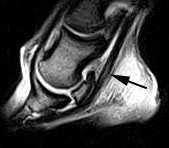

![]() |

| Sagittal image of horse's foot shows lesion on tendon (arrow). |